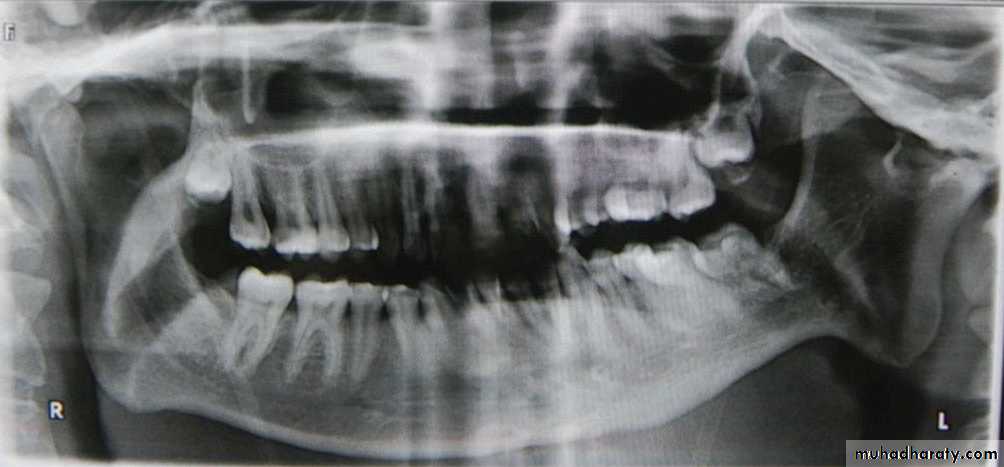

Fractures and trauma:

Fractures of the condylar necks are common after a blow to the chin .With this type of injury the condylar neck does not fracture but the head of the condyle either fractures, a so-called intra-capsular fracture ,or is forced upwards, through the glenoid fossa into the middle cranial fossa .

CT will demonstrate the extent of any injury. Trauma can also result in unilateral or bilateral dislocation .

OPG: showing bilateral dislocation of the

condyles (open arrows) out of the glenoid fossae (white arrows).Developmental anomalies: